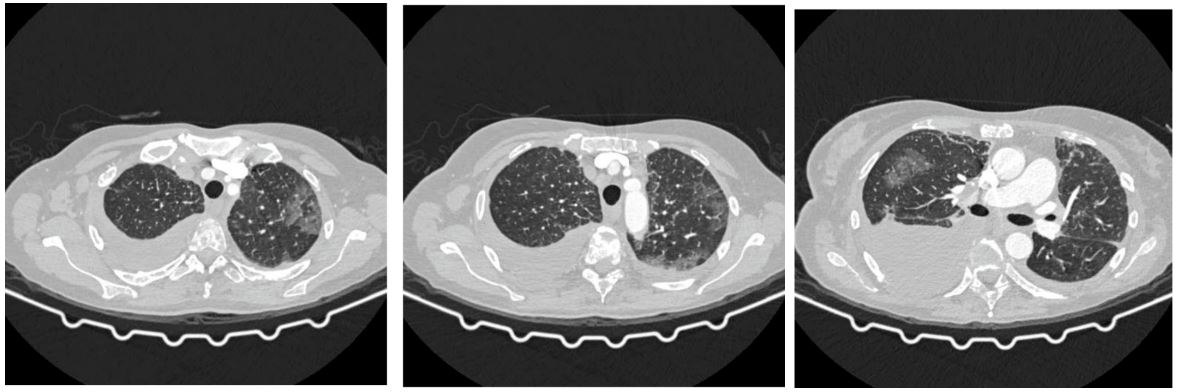

A pleural puncture was performed by a thoracic surgeon, during which approximately 1500 ml of serous content was obtained, which was sent for pathohistological analysis. The pathohistological findings of the pleural punctuate showed a structureless eosinophilic content, a mass of neutrophil granulocytes and erythrocytes, as well as rare mesothelial cells without noticeable malignant cells. Blood and sputum cultures remained sterile, and a comprehensive infectious disease workup was negative. Polymerase chain reactions for atypical pneumonia and respiratory viruses were all negative as well. Therefore, ribociclib was discontinued along with starting methylprednisolone (1.5 mg/kg/day), with noticeable clinical improvement within 1 week. The patient was treated with other symptomatic and supportive therapies, including oxygen therapy (O2 l/min), dual antibiotic therapy with probiotic, LMWH (Low Molecular Weight Heparin), PPI (Proton Pump Inhibitors), diuretic therapy, pain reliever, antiemetic therapy, and internal medicine therapy. Six weeks later, the patient displayed recovery, clinically. Therefore, the steroids were slowly tapered down. Ribociclib was permanently discontinued, Arimidex too. The patient continued treatment with systemic chemotherapy according to the W-Taxol (3+1) protocol. A control CT chest scan, showed that the previously described zones in the lung parenchyma according to the type of GGO are in progression (Figure 2). Other findings are stationary compared to the previous chest scanner.

Figure 2: Chest scanner with GGO-type zones with progression as part of ILD/pneumonitis.

In the MONARCH 3 trial, which compared the combination of abemaciclib and an aromatase inhibitor to an aromatase inhibitor alone in untreated postmenopausal women with HR-positive, HER2-negative locoregionally recurrent or metastatic breast cancer, one patient treated with the combination died from pneumonitis. In the MONARCH 2 trial, which compared the CDK4/6 inhibitor + fulvestrant to fulvestrant alone in women with HR-positive, HER2-negative advanced or metastatic breast cancer who have disease progression following endocrine therapy, two patients died from pneumonitis. The MONARCH 2 trial’s results supported the approval of abemaciclib [11]. According to the prescribing information, cases of interstitial lung disease/pneumonitis were also reported after approval [12]. Ribociclib in combination with an aromatase inhibitor was also approved in 2017 as initial endocrine-based therapy for postmenopausal women with HR-positive, HER2-negative advanced or metastatic breast cancer [11]. There is less evidence showing the link between CDK-4/6 inhibitors and pulmonary toxicity. The articles on pablociclib- and abemaciclib-induced lung injury illustrate the potentially fatal drug-associated lung injury that may be associated with them. After four weeks of ribociclib use, our patient developed pneumonitis, which is uncommonly reported in the medical literature. The multi-slice chest scan revealed ILD/pneumonitis with GGO-type zones that were highlighted on both sides in the upper lobes and the lower left lobe, as well as bilateral pleural effusion (Figure 1). The clinical findings were worse than the radiographic (Figure 1). Therefore, ribociclib was discontinued along with starting methylprednisolone (1.5 mg/kg/day), with noticeable clinical improvement within 1 week. Six week later a control CT chest scan displayed progression of the previously described zones in the lung parenchyma according to the type of GGO (Figure 2). The patient was clinically better, but the control radiographic finding was in progression. Therefore, the pulmonologist prescribed corticosteroid therapy according to the following scheme: 40 mg of prednisone once daily for 3 weeks, then 30 mg of prednisone once daily for a month, then 20 mg of prednisone once daily for 3 months. After 3 months of therapy by a pulmonologist, the patient underwent a control scan of the chest and abdomen, which described a complete regression of zones according to the type of GGO as part of ILD/pneumonitis (Figure 3). In addition, previous real-world study based on the FAERS database showed that a median latency of 63 days (range 21-136) for CDK4/6 inhibitor-associated ILD [1]. This finding was in line with the results from an adverse event-time analysis of abemaciclib and palbociclib using data from Japanese Adverse Drug Event Report (JADER) database, suggesting that both abemaciclib and palbociclib were associated with the onset of ILD after 1-2 months from the start of treatment [29]. A retrospective study of drug-induced ILD demonstrated that, there was a certain similar trend in the timing of the occurrence of ILD induced by most anticancer drugs, most of which occurred within 3 months [30]. There are no known risk factors for the development of lung inflammation associated with CDK4/6 inhibitor use [11]. For patients with severe interstitial lung disease and/or pneumonitis who develope new or worsening pulmonary symptoms, the FDA recommends interrupting treatment and permanently discontinuing CDK4/6 inhibition and initiating corticosteroids [26]. It is essential for clinicians to remember that fatal interstitial pneumonitis can occur in ribociclib-treated patients (even after only four weeks into treatment), as early diagnosis can be crucial [9]. Besides early diagnosis of ILD/pneumonitis proper and continuos usage of corticosteroids is also crucial.